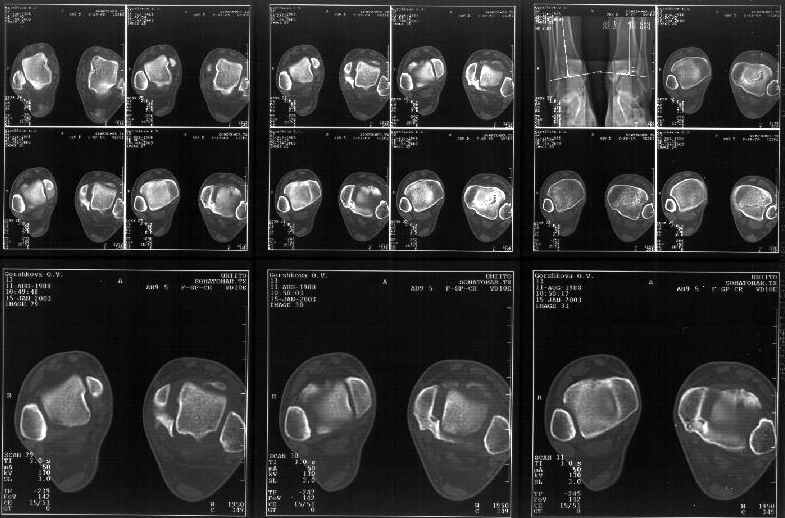

Сегодня пациентке сделали сравнительную КТ. А ксиальные и Фронтальные срезы приложены. Ваше мнение?

Аксиальные

На КТ я попытался изобразить скромными своими способностями (А)- место перелома, (С)- нормальный суставной зазор меж тараном и тремя его маллеолами. (В)- образовавшийся в результате перелома широкий раза в три зазор, позволяющий, по-моему, сублюксацию тарана при ходьбе. В свете данных КТ, критически важных, я бы предложил вертикальную остеотомию места перелома

задне-внутренним подходом и фиксацию мед. маллеола прижатым к тарану с помощью тонкого compression screw. После этого гипсовый сапожок и немедленное расхаживание ноги.